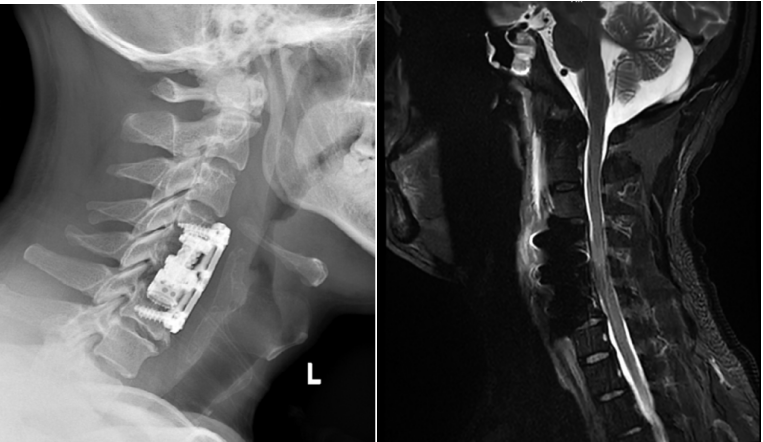

手术后患者X光及核磁共振复查

“手术核心操作用了不到一个小时,新型锥体植入完成后,X光报告人工椎体安得非常好,整个手术室都响起了掌声。”负责此次手术第二助手的蒋奎军医生回忆起当时的场景,仍难掩激动。